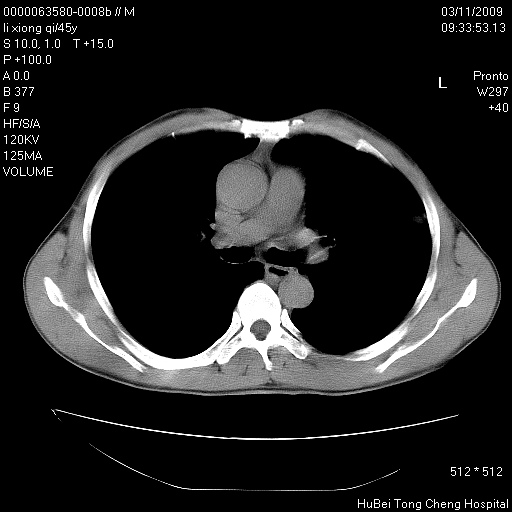

患者 男,45岁。胸痛,咳嗽伴痰中带血1月余。

临床诊断:肺结核?

胸部ct轴位平扫(层厚10mm,螺距1.5,重建间隔10mm),图像如下:

考虑肝癌肺转移

考虑肝癌肺转移。

肝癌肺转移